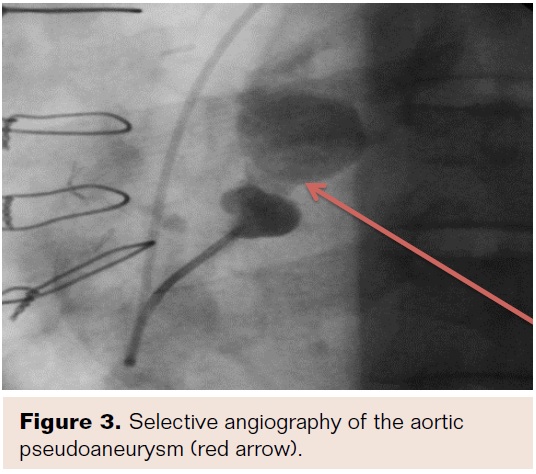

A 57-year-old male presented to his nearest hospital with acute onset of chest pain. His past medical history was significant for a type A aortic dissection repair with a 24 mm Dacron Hemashield graft (Maquet) 2 years prior and subsequent sternal wound infection requiring debridement. Afterward, he developed restrictive physiology and underwent a pericardial stripping via thoracotomy. Computed tomography (CT) scan revealed a large PSA (Figure 1) with a discrete and narrow entry point arising from the ascending aorta near the previous suture line that was confirmed by transesophageal echocardiography (Figure 2). The patient was transferred to our institution for further management. In light of his complex surgical history, a percutaneous transcatheter approach was chosen.